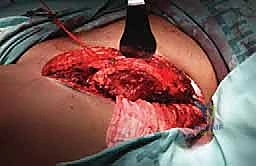

The initial goal is wide, safe exposure of the involved bone, ensuring clear margins for the cortical window while rigorously protecting the soft tissues. The skin incision is placed directly over the planned window, utilizing standard extensile approaches. Fasciocutaneous flaps must be raised meticulously and kept thick to maintain their viability, as they will be exposed to significant thermal stress.

Extensile exposure of the proximal humerus, demonstrating meticulous handling of the soft tissue envelope.

Neurovascular structures are identified early, mobilized gently, and protected with vessel loops and moist laparotomy sponges. Once the bone is exposed, the tourniquet is inflated. Using fluoroscopic guidance, we confirm our anatomical landmarks. The planned cortical window is marked with a sterile pen or electrocautery.

The window must be elliptical to minimize stress risers. We typically outline the window using a high-speed burr or multiple drill holes, which are then carefully connected with sharp osteotomes. The cortical lid is removed and can sometimes be sterilized and replaced later, though it is often discarded if heavily involved with tumor.

Creation of the cortical window using drill holes connected by osteotomes, preserving the structural integrity of the surrounding shaft.